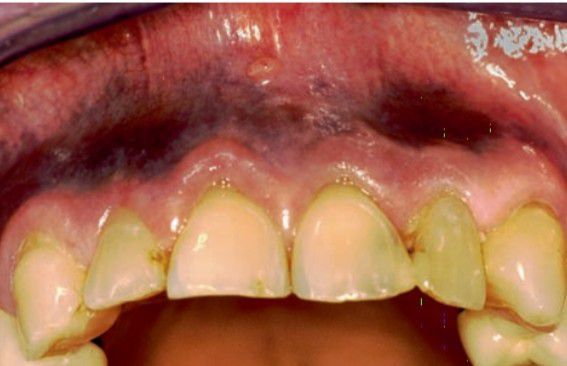

Drug induced pigmentation

This clinical picture shows clofizamine induced pigmentation of oral mucosa